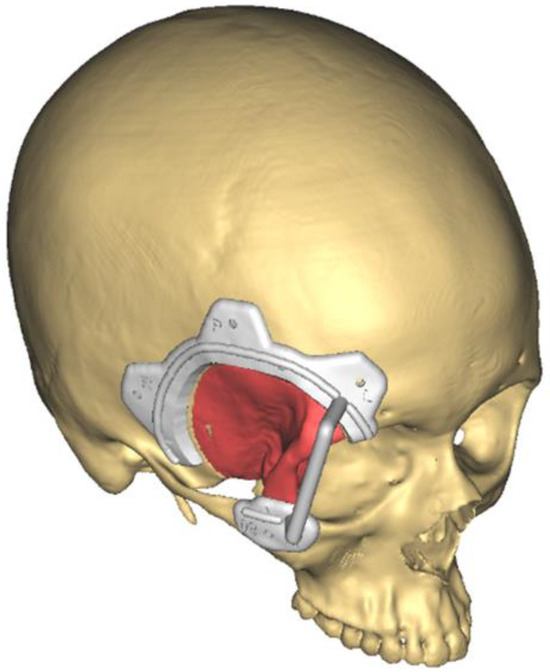

Custom CAD/CAM Peek Implants for Complex Orbitocranial Reconstruction: Our Experience with 15 Patients

4.2. Surgery Virtual Planning: CAD CAM Technology

4.3. Reconstruction with Patient-Customized Implants (PSIs)